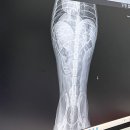

대구 24시 동물병원 수성구 강아지 건강검진 슬개골 정밀 후기 24시 황금동물의료센터 글, 사진 ⓒ장꼬미언니 안녕하세요! 펫인플루언서 장꼬미언니입니다. ​ ​ 오늘은 꼬미와 함께 대구 24시 동물병원이자 실력 있는 수성구 동물병원으로 유명한 ​황금동물의료센터에서 강아지 건강검진을 받고 온 솔직한 후기를 남겨...